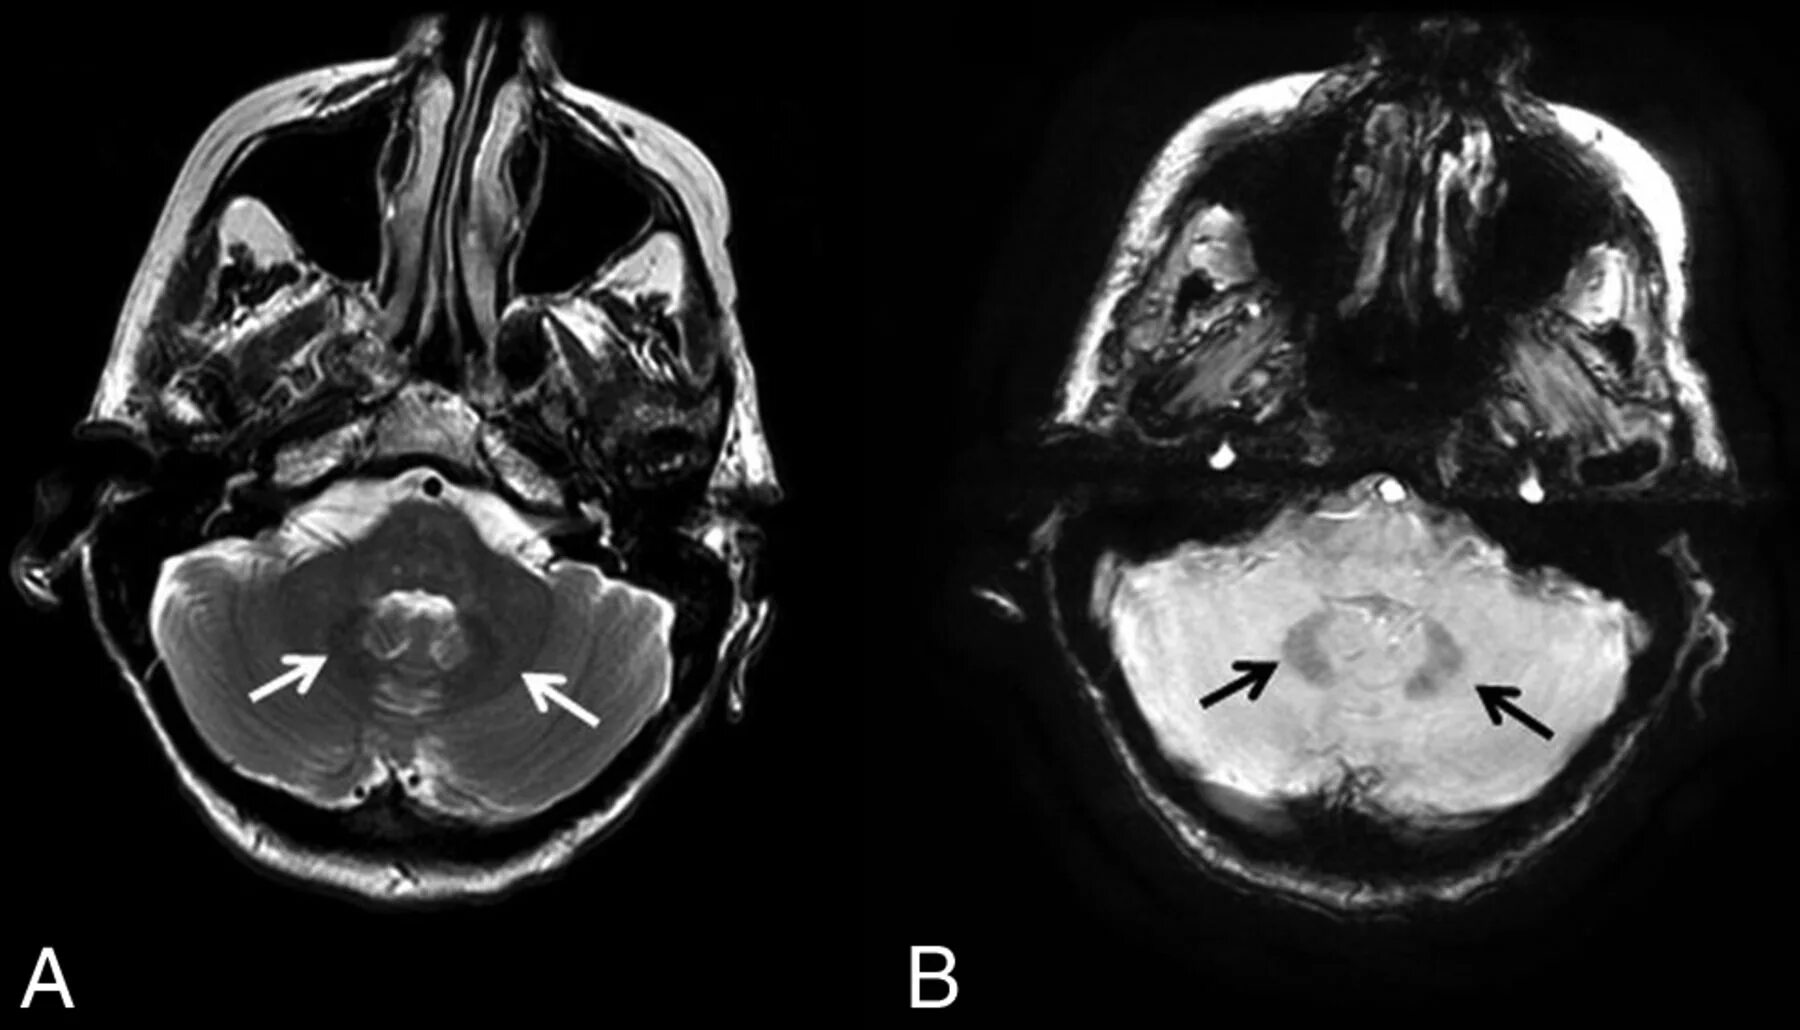

Мрт сигнал